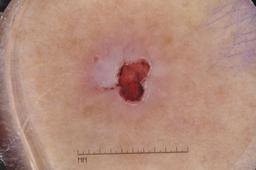

{

"age_approx": 85,

"anatom_site_general": "lower extremity",

"concomitant_biopsy": true,

"dermoscopic_type": "contact non-polarized",

"diagnosis_1": "Malignant",

"diagnosis_2": "Malignant epidermal proliferations",

"diagnosis_3": "Squamous cell carcinoma, NOS",

"diagnosis_confirm_type": "histopathology",

"image_type": "dermoscopic",

"lesion_id": "IL_0375857",

"melanocytic": false,

"sex": "male"

}